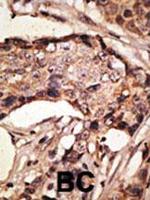

Antibodies that detect SIGLEC9 can be used in several scientific applications, including Western Blot, Immunohistochemistry, Flow Cytometry, Immunocytochemistry and ELISA. These antibodies target SIGLEC9 in Human, Canine, Mouse, Non-human primate and Bovine samples. Our SIGLEC9... Antibodies that detect SIGLEC9 can be used in several scientific applications, including Western Blot, Immunohistochemistry, Flow Cytometry, Immunocytochemistry and ELISA. These antibodies target SIGLEC9 in Human, Canine, Mouse, Non-human primate and Bovine samples. Our SIGLEC9 monoclonal, polyclonal and recombinant... Antibodies that detect SIGLEC9 can be used in several scientific applications, including Western Blot, Immunohistochemistry, Flow Cytometry, Immunocytochemistry and ELISA. These antibodies target SIGLEC9 in Human, Canine, Mouse, Non-human primate and Bovine samples. Our SIGLEC9 monoclonal, polyclonal and recombinant monoclonal antibodies are developed in Mouse, Rabbit and Human. These antibodies have been verified by Cell treatment to confirm specificity to SIGLEC9. Find the SIGLEC9 antibody that fits your needs. Choose from 1 of 21 SIGLEC9 antibodies, which have been validated in experiments with 5 publications and 63 images featured in our data gallery.

Antibodies that detect SIGLEC9 can be used in several scientific applications, including Western Blot, Immunohistochemistry, Flow Cytometry, Immunocytochemistry and ELISA. These antibodies target SIGLEC9 in Human, Canine, Mouse, Non-human primate and Bovine samples. Our SIGLEC9 monoclonal, polyclonal and recombinant monoclonal antibodies are developed in Mouse, Rabbit and Human. These antibodies have been verified by Cell treatment to confirm specificity to SIGLEC9. Find the SIGLEC9 antibody that fits your needs. Choose from 1 of 21 SIGLEC9 antibodies, which have been validated in experiments with 5 publications and 63 images featured in our data gallery.

WB IHC (P)

WB IHC (P) Flow

WB IHC (P) ICC/IF